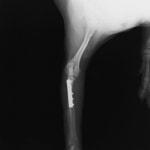

症例:交通事故による椎体脱臼

柴犬:9歳、避妊雌

交通事故直後、胸腰部に激しい疼痛、両後肢に完全麻痺を認め、シェフシェリントン徴候を呈していました。レントゲン検査において、第11-12胸椎間の脱臼が認められました。

脊髄の減圧、脊柱管の再構築・安定化を目的に、片側椎弓切除術およびMatrixMANDIBLE Plateによる椎体固定を実施しました。

隣接椎体を架橋するようにプレートを設置しました。

術後レントゲン写真